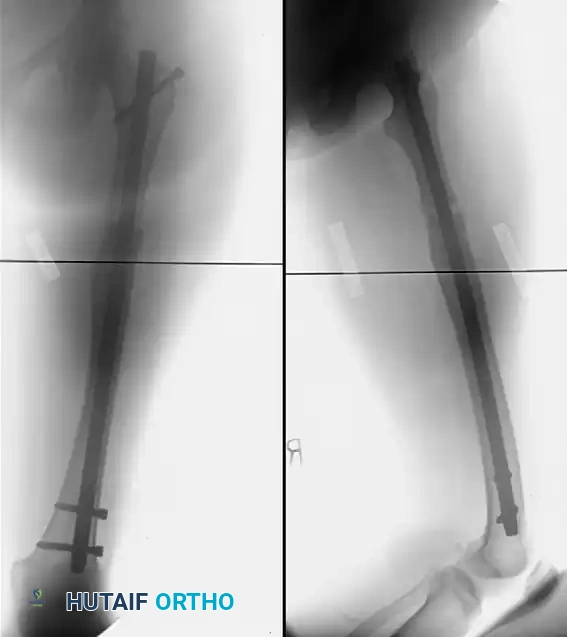

FIGURE 58-24 C: Postoperative AP radiograph following corrective osteotomy, removal of the previous implant, and rigid fixation with a proximal interlocking Grosse-Kempf medullary nail.

Image

FIGURE 58-24 D: Postoperative lateral radiograph confirming restoration of sagittal alignment and rotation.